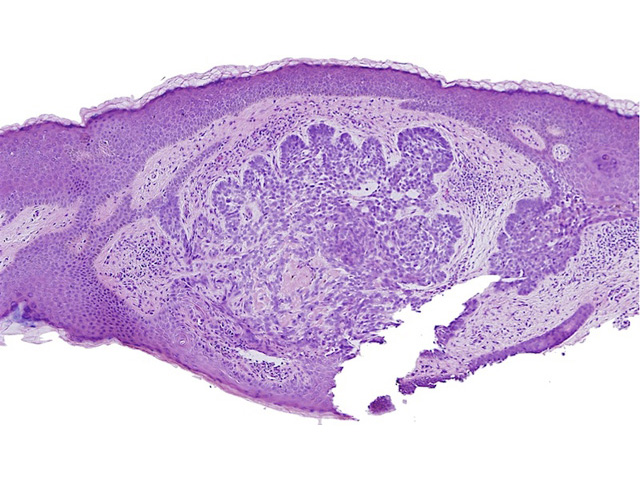

BCC on histopathology

OCT

Images courtesy of Dr Orit Markowitz. In the right hand example, the dark halo encompassing the BCC tumour on OCT (bottom) is a characteristic finding for BCC nests. This feature includes both the mucinous cleft and the peripheral palisading evident on histology sections (top).